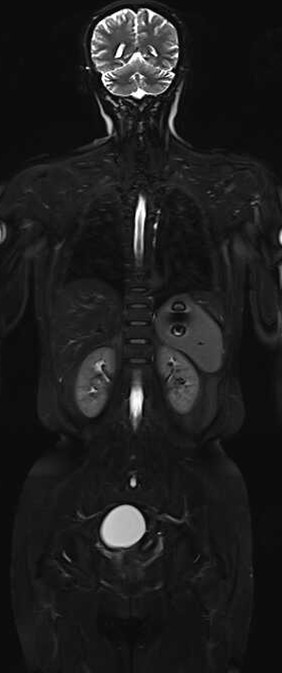

Lumina 3T智能磁体具备业内最大成像范围55cm,能够得到完整大范围静态和动态高清成像

Lumina 3T同时具备业内大孔径,70cm的检查孔径,能够为患者提供更宽敞和舒适的检查环境,适应危重、肥胖、幽闭综合症患者检查,减少受检过程中压抑、沉闷等不良感受。